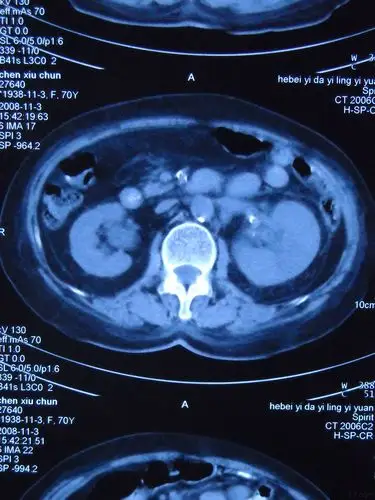

ct:左肾癌肾癌是泌尿外科常见的疾病,我见过最年轻的成年人肾癌患者是

复杂性肾囊肿和囊性肾癌的鉴别诊断 - 好大夫在线